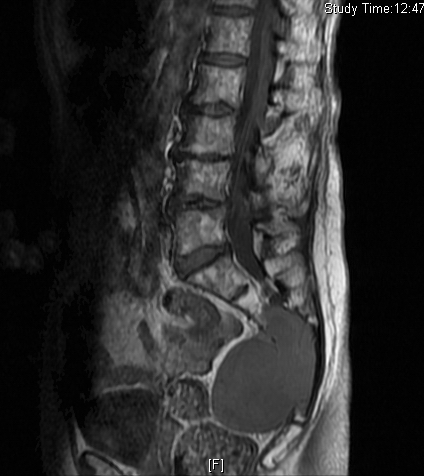

MRI (Fig. 4-10)

• Isointense or hypointense on T1W (Fig. 4-5)

Fig. 4-10: MR image of a chordoma shows a destructive bone lesion in the sacrum that is hypointense on T1W images, hyperintense signal on T2W and enhancement of the lesion after gadolinium.